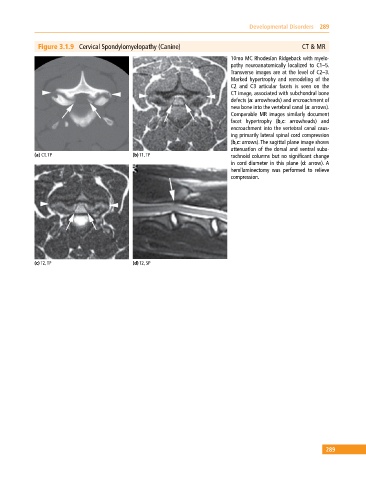

Figure 3.1.9 Cervical Spondylomyelopathy (Canine) CT & MR

10mo MC Rhodesian Ridgeback with myelo

pathy neuroanatomically localized to C1–5.

Transverse images are at the level of C2–3.

Marked hypertrophy and remodeling of the

C2 and C3 articular facets is seen on the

CT image, associated with subchondral bone

defects (a: arrowheads) and encroachment of

new bone into the vertebral canal (a: arrows).

Comparable MR images similarly document

facet hypertrophy (b,c: arrowheads) and

encroachment into the vertebral canal caus

ing primarily lateral spinal cord compression

(b,c: arrows). The sagittal plane image shows

attenuation of the dorsal and ventral suba

(a) CT, TP (b) T1, TP rachnoid columns but no significant change

in cord diameter in this plane (d: arrow). A

hemilaminectomy was performed to relieve

compression.